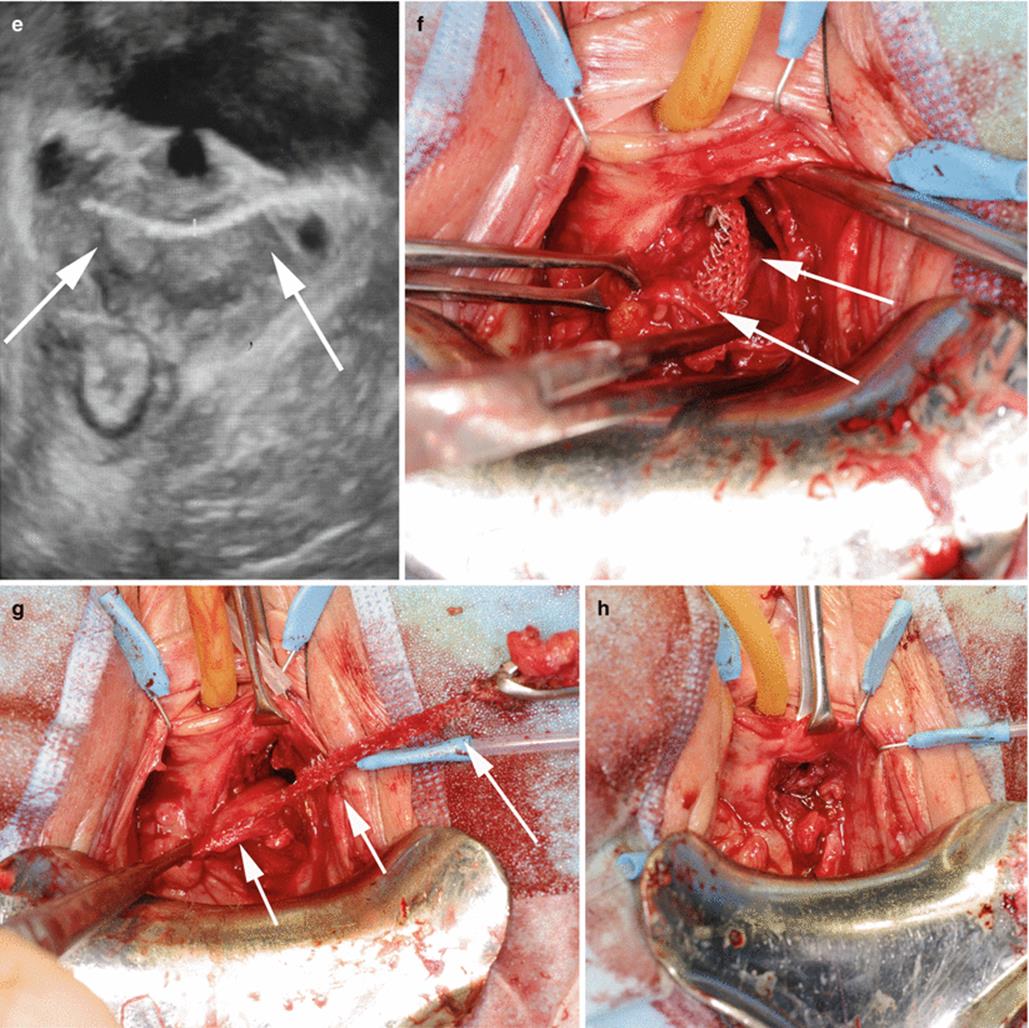

Fig. 9.10

(a) Cystoscopy of a patient with frequency, urgency, pain, hematuria, and recurrent urinary infection after insertion of an anterior vaginal wall mesh. The mesh traversed the bladder from the trigone to the right lateral bladder wall. (b) Exposure of the anterior vaginal wall is obtained and the mesh is dissected from the trigone. A ureteric stent was inserted in the right ureter. The bladder was opened and the mesh was excised from the bladder wall. (c) The bladder is closed in layers. An in situ Martius (arrow), a flap is created and rotated to cover the area of surgery. A retropubic flat drain is inseted (arrow). (d) A flap of the anterior vaginal wall is advanced to cover the area of the reconstruction. (e) Translabial ultrasound in a patient complaining of pelvic pain, urinary infections, and hematuria after insertion of a retropubic mesh. The arrows outline the periurethral mesh. (f) Cystoscopy revealed that the mesh has eroded the left half of the bladder wall. Transvaginal exploration of the left perivesical space is performed, the bladder is opened, and the eroded mesh is exposed (arrow). (g) Suprapubic exploration is performed, and the mesh is transferred through the retropubic space from the abdominal to the vaginal incision (arrow). A transvaginal partial cystectomy is performed because of the extent of the inflammatory changes and stones. The bladder is irrigated with diluted indigo carmine to ensure integrity of the closure. (h) The bladder wall is closed in two layers, and a Martius flap from the left labium is rotated to the left retropubic space